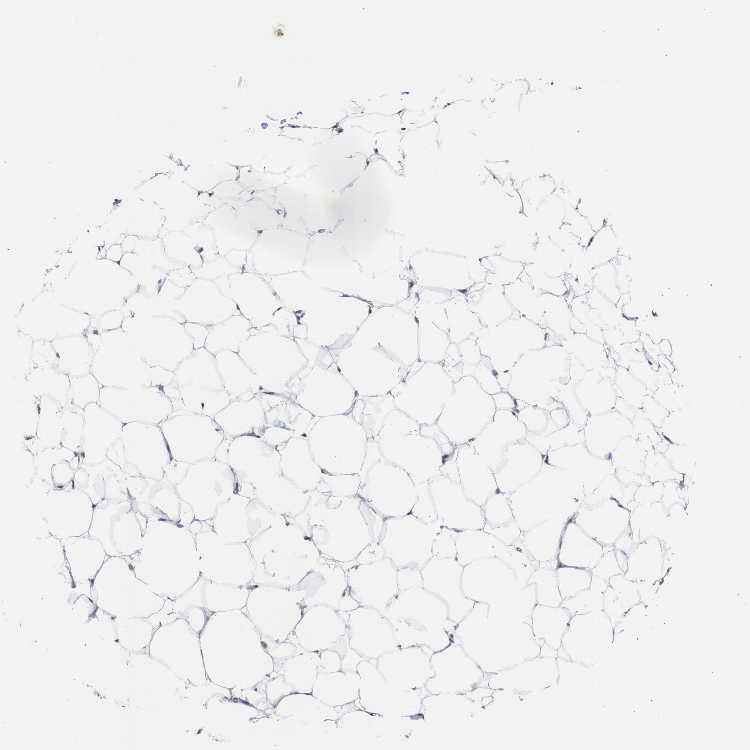

SOFT TISSUE 1 - Antibody stainingi

Antibody staining in the annotated cell types in the current human tissue is reported as not detected, low, medium, or high, based on conventional immunohistochemistry profiling in selected tissues. This score is based on the combination of the staining intensity and fraction of stained cells.

Each image is clickable and will lead to virtual microscopy that enables deeper exploration of all samples and also displays staining intensity scores, fraction scores and subcellular localization as well as patient and tissue information for each sample.

Antibody HPA006912

Fibroblasts Medium